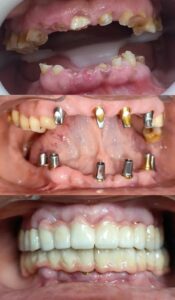

- Implant Placement

During the procedure, four titanium dental implants are surgically placed into the jawbone. Two implants are placed vertically at the front of the jaw, while the other two are angled toward the back to provide maximum stability.

- Temporary Teeth Placement

In many cases, a temporary set of fixed teeth can be attached on the same day, allowing patients to leave the clinic with a functional smile.

- Final Prosthesis

After a healing period of a few months, during which the implants fuse with the bone (a process called osseointegration), the final custom-made prosthetic teeth are attached.